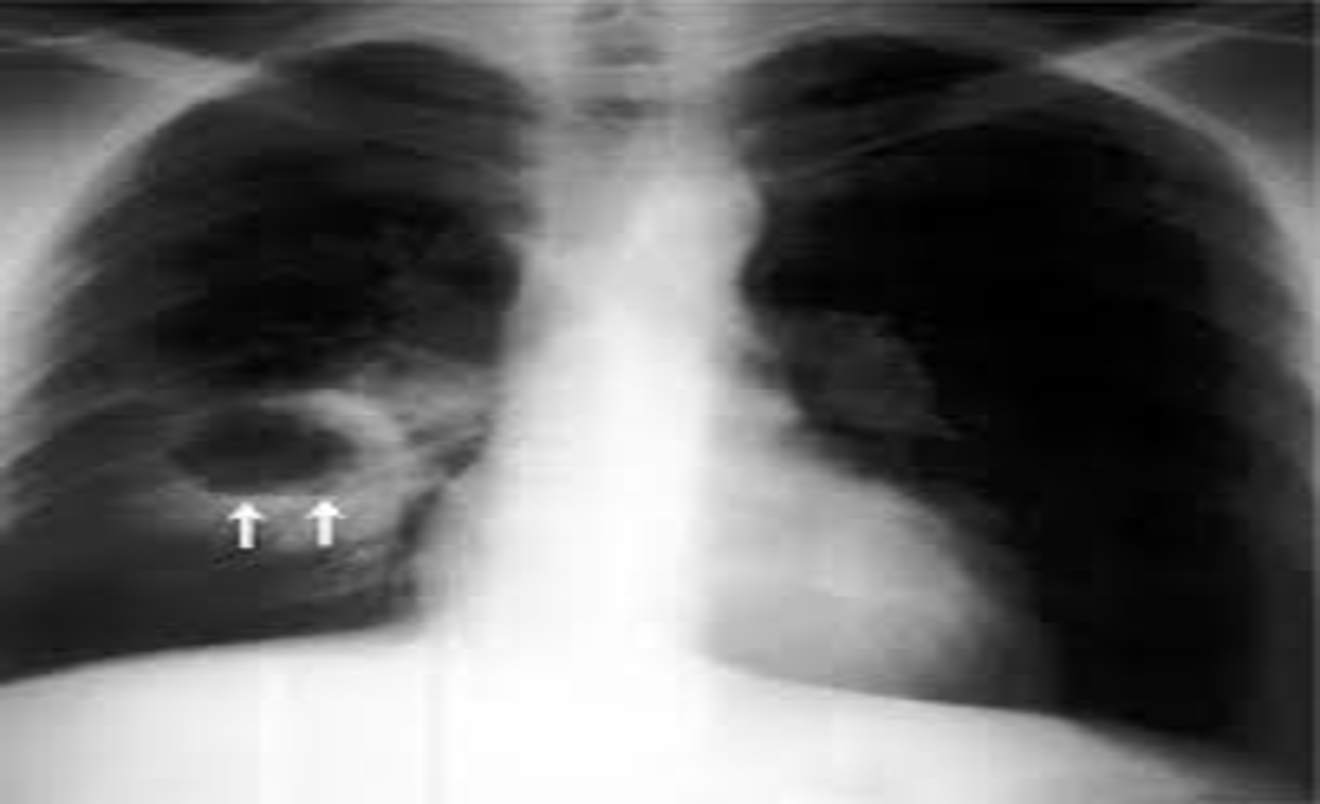

Anterior view of a chest radiograph in a patient with thick-walled right lung abscess. The patient later developed a brain abscess.

Air fluid level

The diagnosis is suggested by a chest radiograph demonstrating a thick-walled cavity with an air-fluid level and confirmed by contrast-enhanced computed tomography .

The air is then seen as a transradiancy within the consolidation and an air–fluid level may be present